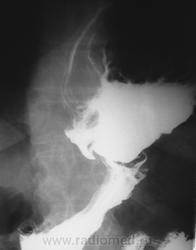

Рентгеноскопия желудка (верхнего отдела желудочно-кишечного тракта): Акт глотания не нарушен. Пищевод свободно проходим до нижней трети грудного отдела, ниже определяется задержка продвижения контраста; контрастированный участок значительно расширен, создаётся впечатление, что последний является кариофундальным отделом желудка. Сам пищевод не укорочен, переходит в желудок в обычном месте.